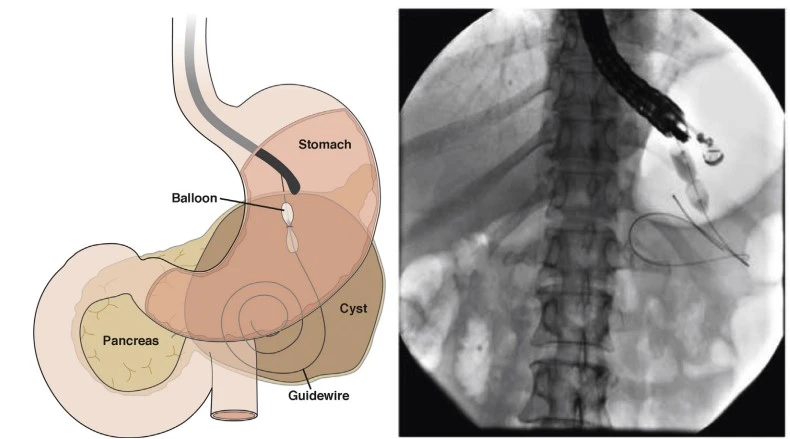

- EUS - Endoscopic ultrasound